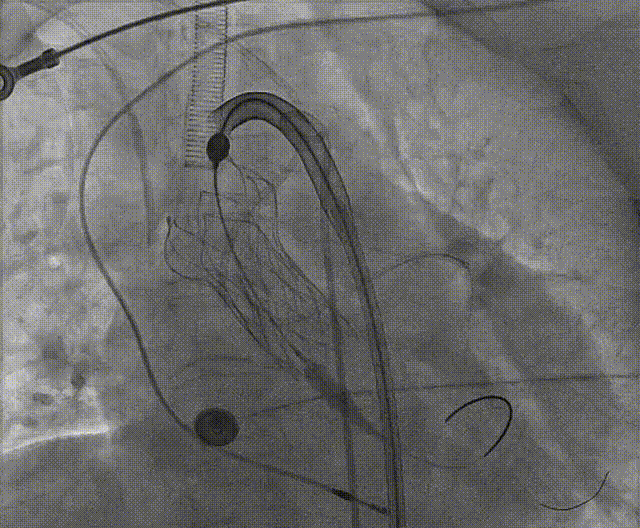

手术流程概括

根部造影

左冠脉提前植入延长导管,预埋冠脉导丝。

20mm球囊预扩张,无腰征,无造影剂泄露。

vitaflow tav24瓣膜轻松过弓初始定位瓣环0位开始释放,班第一次释放瓣膜在转移到瓣上,综合决定回收采取第二次瓣膜释放。

第二次精准零位释放,决定完全释放。

释放后多体位观察造影,瓣膜位置良好,展开良好,轻微瓣周漏。